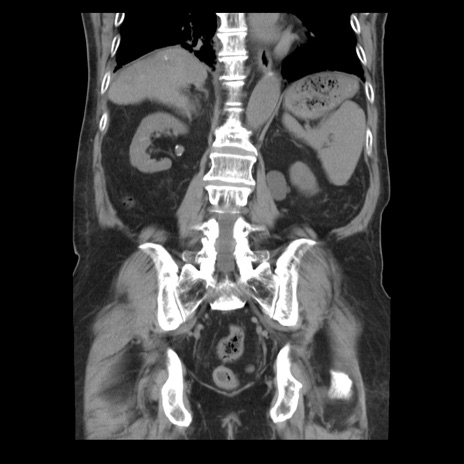

症例21(冠状断像)

【症例】70歳代男性

【主訴】腹痛

【現病歴】肝硬変・肝細胞癌にてかかりつけの方。約9時間前に食後より腹痛出現。症状が徐々に増悪し、嘔吐出現したため来院。

【既往歴】肝硬変、肝細胞癌(RFA、TACE後)

【身体所見】意識清明、表情苦悶様、BT 36℃、BP 129/78mmHg、P 88bpm、SpO2 97%(RA)、右上腹部から心窩部にかけて圧痛あり、反跳痛なし、筋性防御あり。

【データ】WBC 5800、CRP 0.16